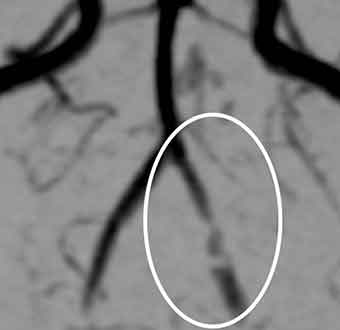

頭部MRA検査を見たところ、

後大脳動脈が所々で途切れたようになっており、可逆性脳血管攣縮症候群と診断しました。